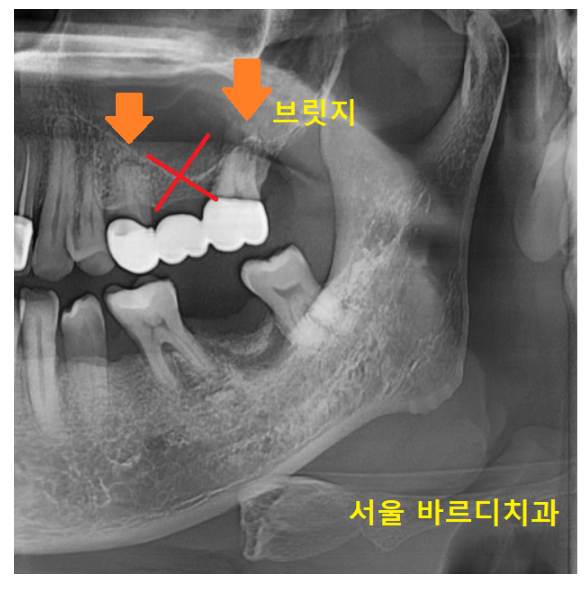

이렇게 치아가 많이 쓰러진 경우

임플란트가 개발되기 전 치료방법 "브릿지" 로 치료합니다.

221218

이렇게 양 옆 치아가 치아 없는 부분을 대체하는 치료가 브릿지인데요

-

수술을 안 해도 된다.

치료 기간이 빠르게 해결된다

2가지 장점이 있지만

브릿지 치료방법의

치명적인 단점이 있습니다.

씌워놓았던 치아 1개가 충치가 생겨

머리 부분이 부러졌습니다.

1개 치아에 문제가 생겼지만

브릿지 치료는 다같이 묶어 놓는다는게 제일 큰 문제입니다.

각각 치료한 치아는

문제가 생긴 치아만 건들이면 되지만

브릿지는 통째로 치료를 다시 해야하거든요~

그 얘기는

다른 치아가 문제가 없어도

벗겨내야 한다는 말이에요~!